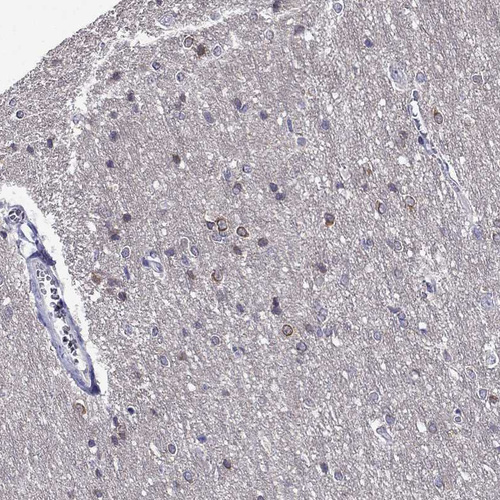

Immunohistochemistry analysis in human cerebral cortex and skeletal muscle tissues using HPA078302 antibody. Corresponding KCNJ10 RNA-seq data are presented for the same tissues.